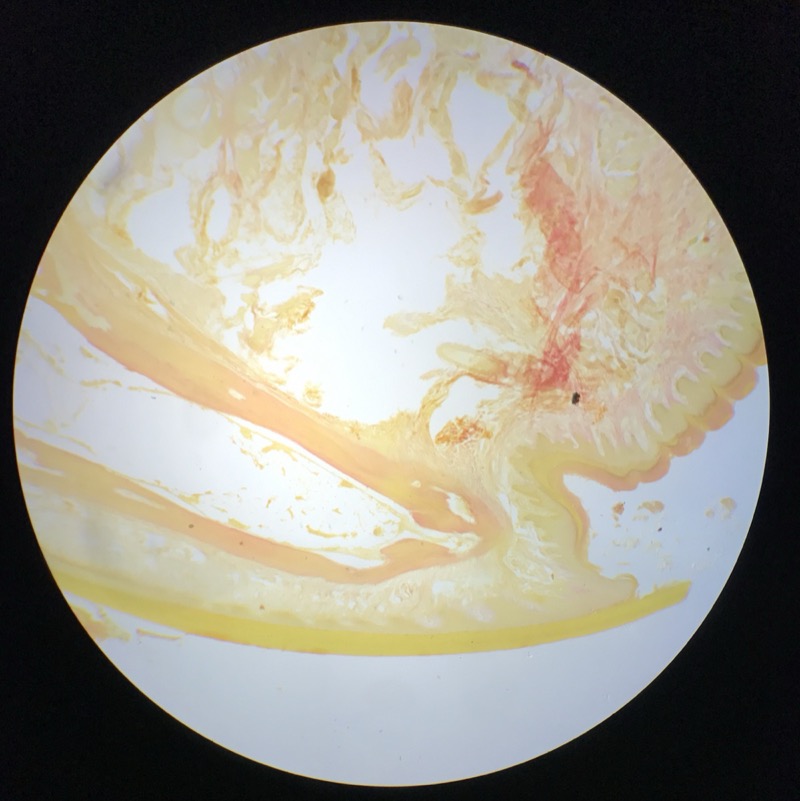

| 1:5:6 | Nagel | ![]() ![]() ![]() ![]() ![]() |